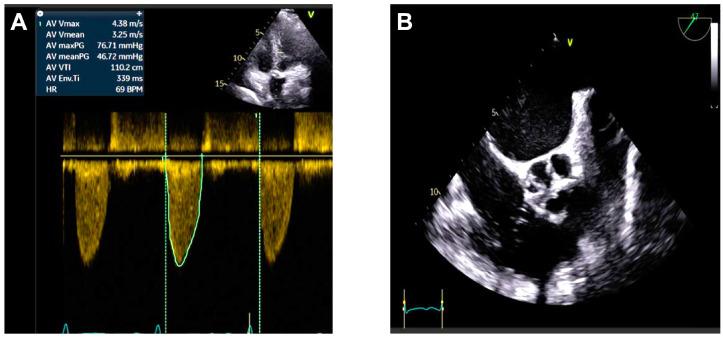

Heyde syndrome is a rare condition characterized by the triad of severe aortic stenosis, gastrointestinal bleeding, and acquired type 2A von Willebrand syndrome. This case report highlights the diagnostic and therapeutic approach for a 72-year-old woman presenting with exertional chest pain, dyspnea, fatigue, and a history of melena. The diagnostic workup revealed severe microcytic anemia and a reduced vWF ristocetin-to-antigen ratio. Imaging confirmed severe degenerative aortic stenosis, while video capsule endoscopy identified angiodysplasia and telangiectasias in the small bowel as the source of gastrointestinal bleeding. Following evaluation by a multidisciplinary Heart Team, the patient underwent transcatheter aortic valve replacement (TAVR) with an Evolut Fx self-expanding prosthesis. Post-procedural echocardiography showed mild paravalvular regurgitation. The patient's clinical course was favorable, with resolution of anemia and no further gastrointestinal bleeding episodes. Heyde syndrome requires a high index of suspicion for diagnosis in patients with severe aortic stenosis and unexplained anemia or gastrointestinal bleeding. TAVR offers an effective treatment option that not only resolves valvular pathology, but also mitigates associated bleeding risks.